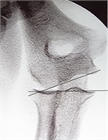

1. 肘関節脱臼・骨折などに伴う急性靱帯損傷で肘関節不安定性がある場合には、一次的靭帯修復を行うことが推奨される。